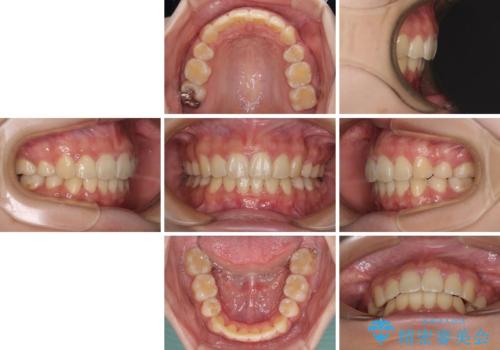

部分矯正で出っ歯になった 出っ歯改善の抜歯矯正

治療後には口が閉じやすくなり、患者様には大変満足していただきました。